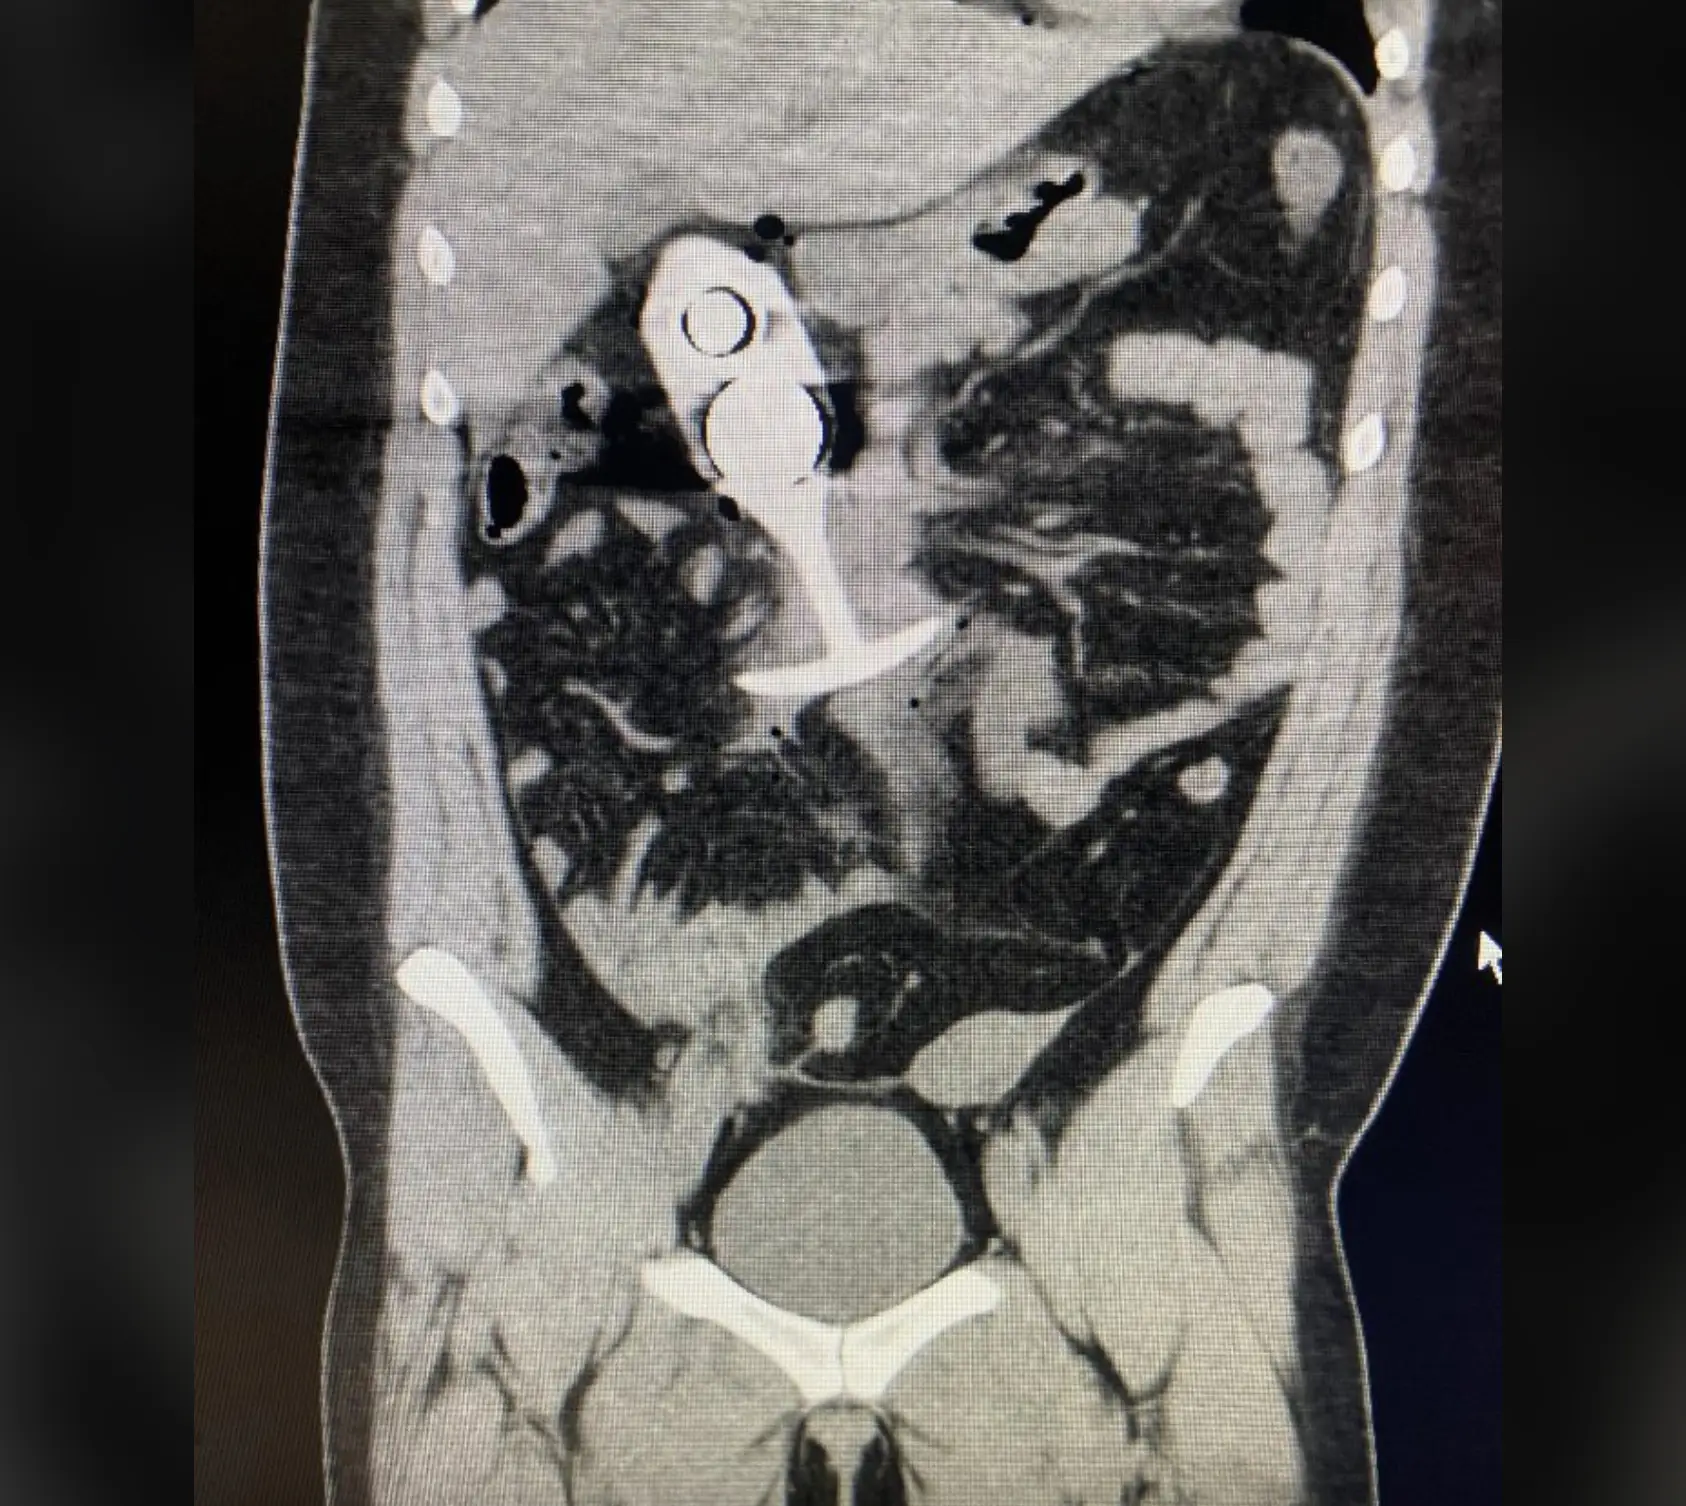

An image of the toy has been circulating online, much to the horror of social media users.

The picture of the alleged incident was shared by X (formerly Twitter) user 'DreadPirateZero', who wrote: " "Never wear a butt plug to your MRI appointment. My god...."